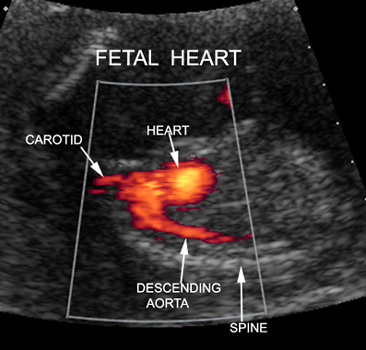

Doppler Fetal Heart |

Fetal Heart |